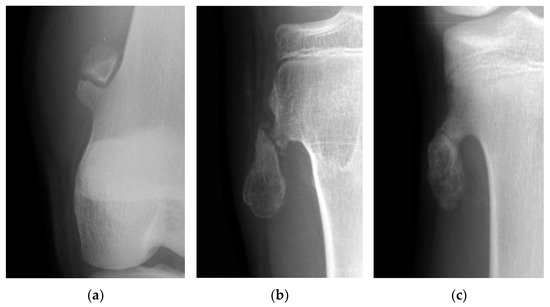

Figure 2.

(a) The picture shows a gap widening of more than 1 mm between fragments of an osteochondroma in the femur. (b) The picture shows a more than 50% translation of a fractured osteochondroma in the tibia. (c) The picture shows a fractured osteochondroma in the tibia from the non-displacement group.